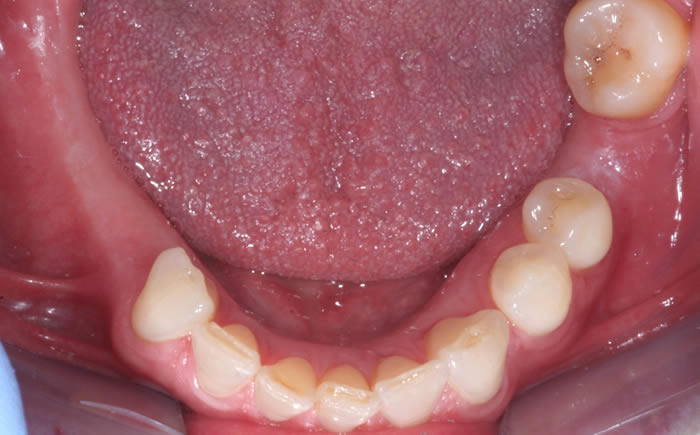

More back teeth replaced by dental implants

Case Three (2 images)